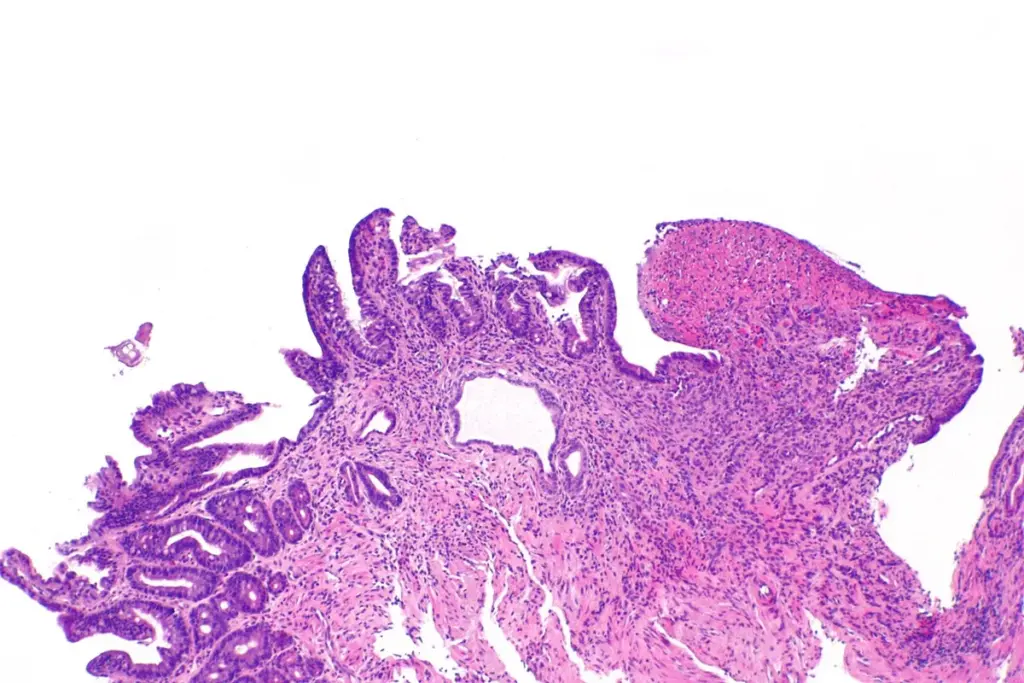

In some clinical cases, the sore can erode through a blood vessel, leading to internal bleeding. This is a serious complication that presents with specific “red flag” symptoms.

A perforation occurs when the sore eats completely through the wall of the stomach or intestine. This allows digestive juices and bacteria to leak into the abdominal cavity.